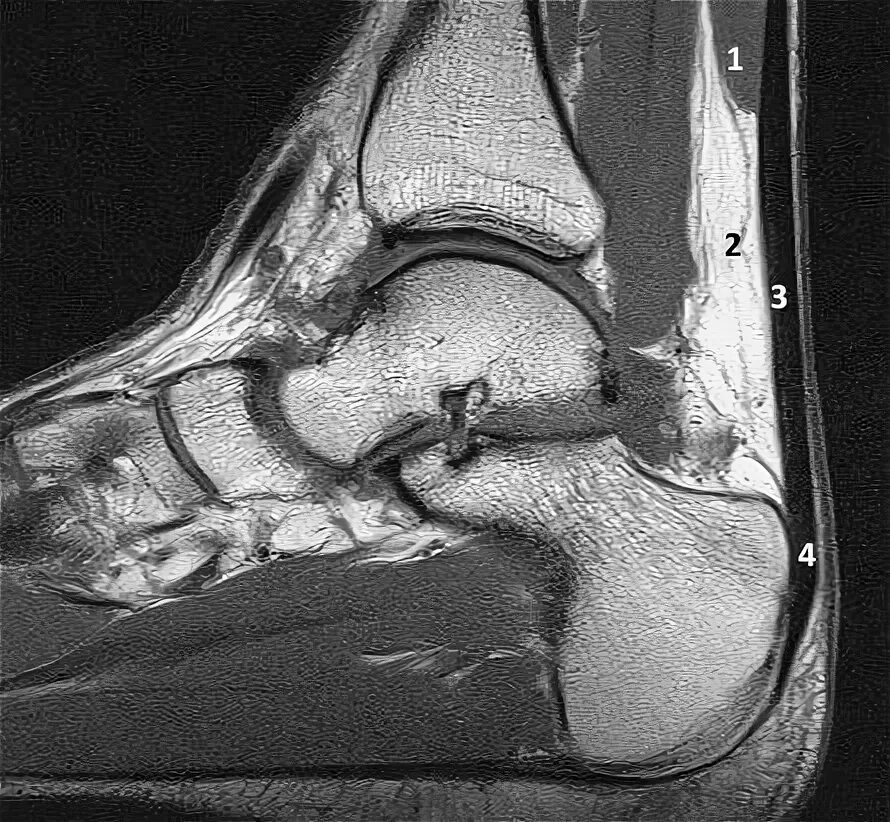

Мрт ахиллового сухожилия